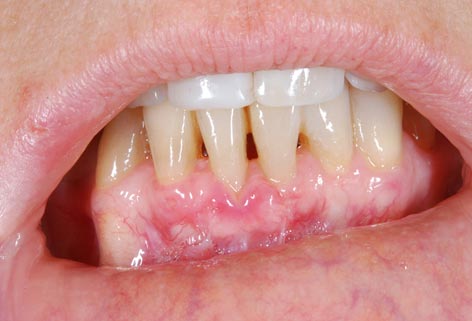

I denti irrecuperabili dell'arcata superiore ed inferiore del paziente di anni 65

sono stati sostituiti da 10 impianti, cioè protesi radicolari endo-ossee che sostengono le protesi fisse superiore ed inferiore.